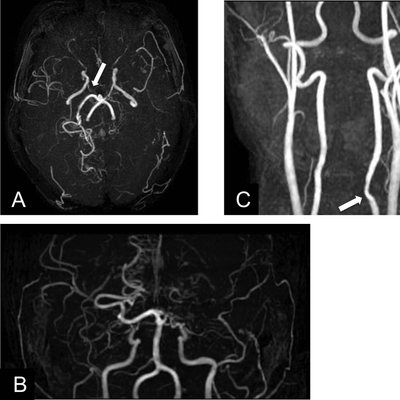

Click on an image below to view more info.